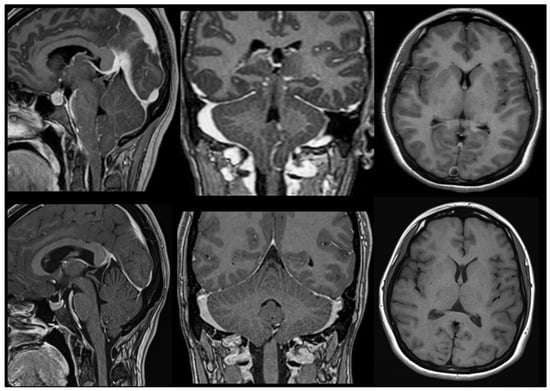

12.2. CM2 and Spina Bifida

14. The Chiari 1.5 Malformation (CM1.5)